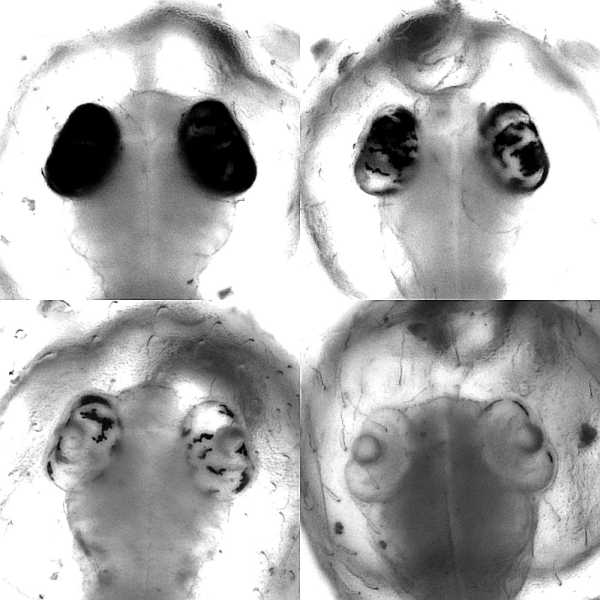

Dass Base-Editoren im lebenden Organismus mit großer Effizienz arbeiten und sich sogar für ein genetisches Screening eignen, haben die Heidelberger Wissenschaftler in einer weiteren Studie nachgewiesen. Im Versuch mit Japanischen Reiskärpflingen konnten sie zeigen, dass diese lokal begrenzten, gezielten Veränderungen einzelner DNA-Bausteine eine Wirkung entfalten, die sonst nur durch die vergleichsweise aufwändige Zucht von Organismen mit verändertem Erbgut erreicht wird. Das Forschungsteam am COS hat dabei in Zusammenarbeit mit Dr. Dr. Jakob Gierten, Kinderkardiologe am Universitätsklinikum Heidelberg, bestimmte Genmutationen in den Blick genommen.

Diese Mutationen standen im Verdacht, angeborene Herzfehler beim Menschen auszulösen. Durch die Veränderung einzelner DNA-Bausteine der entsprechenden Gene im Modellorganismus konnten die Wissenschaftler Fischembryonen mit den beschriebenen Herzfehlern nachahmen und studieren. Der gezielte Eingriff führte bereits in den frühen Embryonalstadien der Fische zu sichtbaren Veränderungen am Herzen, wie Doktorandin Bettina Welz und Dr. Alex Cornean, zwei der Erstautoren der Studie aus dem Team von Prof. Wittbrodt, ausführen. Dadurch konnten die Forscherinnen und Forscher den ursprünglichen Verdacht bestätigen und einen ursächlichen Zusammenhang zwischen genetischer Veränderung und Krankheitsbild herstellen.

Ermöglicht wurde der präzise Eingriff in das Erbgut der Fischembryonen durch die eigens entwickelte, online verfügbare Software ACEofBASEs. Damit lassen sich Stellen in Genen identifizieren, die sehr effizient zu gewünschten Veränderungen an den Zielgenen und daraus resultierenden Proteinen führen. Der Japanische Reiskärpfling ist dabei, so die Wissenschaftler, ein exzellenter genetischer Modellorganismus, um Mutationen zu modellieren, wie sie bei dem jeweiligen Patienten auftreten. „Unsere Methode ermöglicht eine effiziente Screening-Analyse und könnte damit einen Startpunkt für die Entwicklung individualisierter medizinischer Behandlung bieten“, so Jakob Gierten.